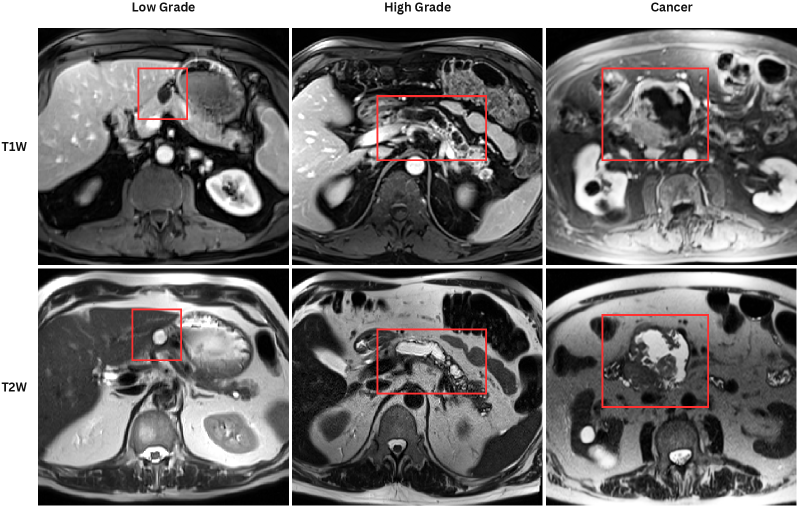

Each patient was categorized into one of these three ground truth classes: no risk/control, IPMN low-risk, or IPMN high-risk. To evaluate variability in image acquisition, we applied uniform manifold approximation and projection (UMAP) to image quality indicators, revealing distinct clustering patterns by imaging center and slice thickness. This heterogeneity reflects real-world clinical variability, enhancing the dataset’s generalizability while presenting technical challenges for model development. Fig. 6 shows examples of low-grade, high-grade, and cancer developing IPMNs from the Cyst-X dataset.